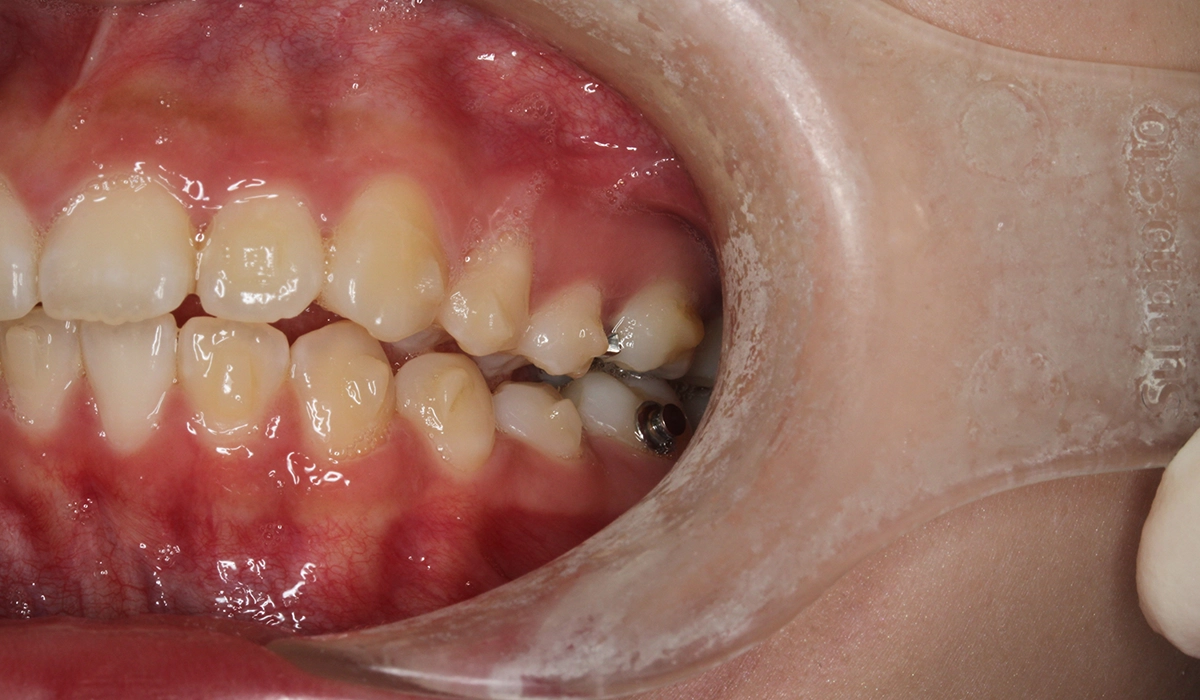

術前:左側

術後:左側